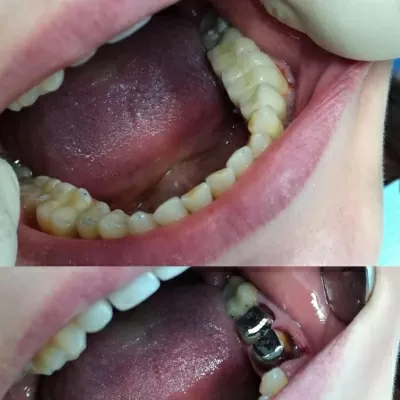

С лета 2018 лечусь в клинике Лигадент у доктора Трошян Тиграна Гамлетовича. За это время доктор восстановил мне все зубы, при лечении которых ранее были допущены, мягко говоря, ошибки. Произвел впечатление очень ответственного, грамотного, образованного специалиста с большим опытом, Это настоящее счастье, когда с тобой работает профессионал такого уровня! Далее мне поставили читать далее